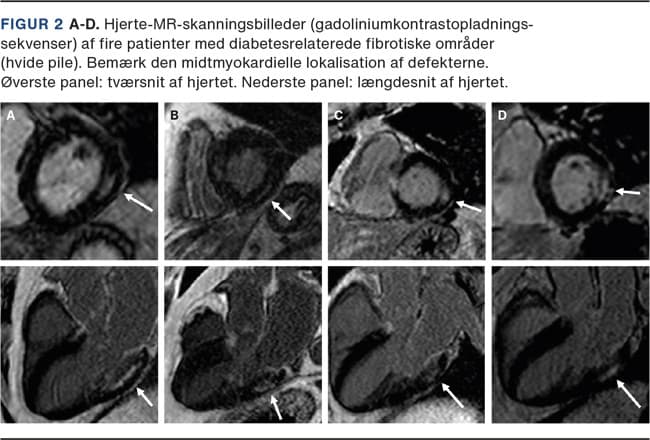

Historisk var det den danske læge Knud Lundbæk, der i 1954 beskrev de særegne diabetiske karforandringer ved DM [22], og det var også Lundbæk, der i 1969 foreslog, at DM måske gav ophav til en egentlig »diabetisk kardiomyopati« [23]. I 1970’erne viste flere mindre patologistudier af patienter, der havde DM og døde med tegn på inkompenseret hjertesygdom, at HF kunne være associeret med stive hjerter med udbredt fibrosedannelse og ophobning af »avancerede glykerede endeprodukter« (AGEs) [24]. Nogle af patienterne have deciderede »øer af fibrose«, der ikke var relateret til IHD [24], idet deres koronararterier var uden signifikant aterosklerose, og fibrosedannelse ved IHD altid udgår fra subendokardiet, hvor de fibrotiske øer hos patienterne med DM var lokaliseret midtmyokardielt. Lundbæk havde altså ret: DM giver ophav til en specifik kardiomyopati, der ikke behøver at være associeret til IHD. Disse studier er i dag vidtgående glemt, men forståelsen af, at DM giver anledning til diffus fibrosedannelse af myokardiet, udtyndede koronararterier (et fund, der også kendes fra koronarangiografier af patienter med DM) og stive hypertrofiske ventrikler, er nu velkendt.

Bojer AS, Sørensen MH, Vejlstrup N et al. Distinct non-ischemic myocardial late gadolinium enhancement lesions in patients with type 2 diabetes. Cardiovasc Diabetol. 2020;19(1):184.